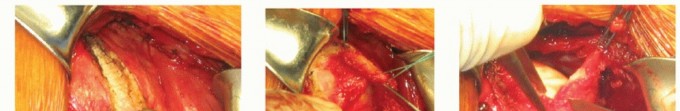

TECH FIG 1 • Bankart procedure. A. The deltopectoral interval is identified and incised using a needle-tip Bovie. The cephalic vein is retracted laterally with the deltoid. B. The anterolateral leading edge of the coracoacromial ligament (indicated by the clamp) is resected for improved superior exposure. C. The subscapularis is incised about 1 cm medial to its insertion, leaving a stout cuff of tissue laterally (arrow) for subsequent repair. (continued)

The subscapularis tendon is exposed and incised vertically just medial to its insertion. The tendon can be peeled off the underlying capsule with a combination of the periosteal elevator for blunt dissection and the needle-tip Bovie cautery for sharp dissection (TECH FIG 1C,D).

The anterior capsule is then incised vertically at the level of the glenoid rim (TECH FIG 1E,F).

With a curette or osteotome, the anterior glenoid rim is roughened and any soft tissue removed to expose a bleeding bony bed to facilitate healing of the repair (TECH FIG 1G).

Transosseous sutures are passed through holes made with pointed forceps or a drill. Alternatively, suture anchors may be placed at the margin of remaining articular cartilage.

Often, two and, sometimes, three anchors are used between the 2:30 and 6 o'clock positions (in a right shoulder) (TECH FIG 1H).

The capsule is shifted or repaired anatomically as required. Typically, an inferior capsular shift procedure is performed in combination with the Bankart procedure as described in the following texts.

The subscapularis tendon is repaired anatomically at its insertion. Secure repair of the subscapularis tendon is important to prevent postoperative disruption.

TECH FIG 1 • (continued) D. Blunt dissection inferiorly, where the subscapularis muscle is not adherent to the capsule, facilitates in finding the plane of separation between the subscapularis and anterior capsule. E. The capsule is sharply incised, taking care not to damage the humeral head cartilage below. F. An adequate cuff of tissue is left behind for subsequent repair. G. The glenoid rim is prepared using an osteotome or curette. H. Suture anchors are placed at the apex of the glenoid rim. 1. ## T-Plasty Modification of the Bankart Procedure